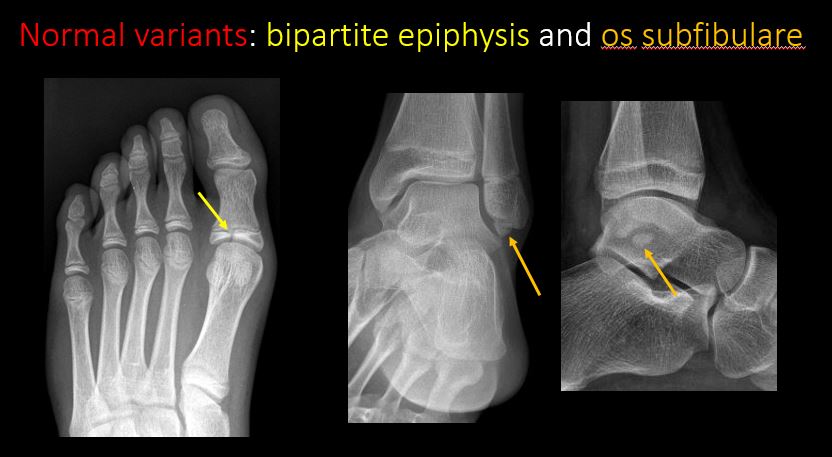

The apophysis, epicondyle, secondary ossification center, or accessory ossicle is displaced or otherwise abnormal (e.g. avulsed ASIS, medial epicondyle of the humerus, etc). [Yes/No]

There are developmental changes or other anatomic variants or other existing conditions that may or may not be contributing to symptoms which can or should be further evaluated non-emergently or are otherwise incidental. [Yes/No]